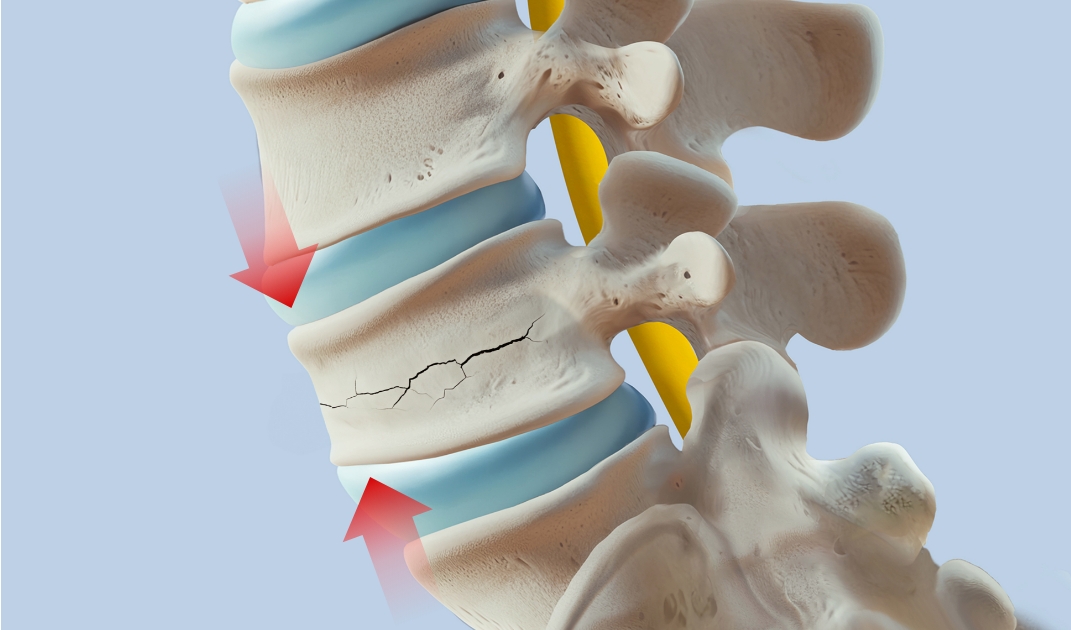

척추압박골절이란?

척추뼈의 앞 부분이 크고 작은 충격에 의해 눌려

납작하게 주저앉아 생긴 골절상태